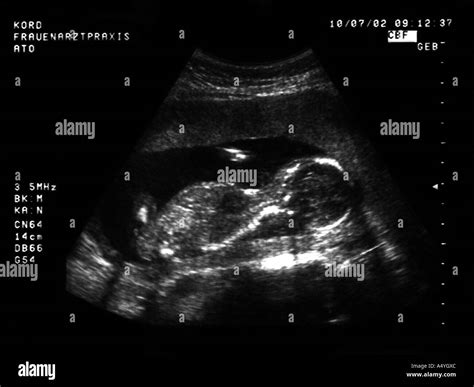

In der 33. Schwangerschaftswoche können werdende Eltern, trotz positiver ärztlicher Einschätzung, Sorgen bezüglich der Ultraschallbilder entwickeln. Insbesondere die Darstellung der Lippen und der Mundpartie des Kindes im Ultraschall kann Anlass zu Fragen geben. Es ist wichtig zu verstehen, dass ein Ultraschallbild kein statisches Foto ist, sondern eine Momentaufnahme, die durch verschiedene Faktoren beeinflusst wird.

Die scheinbar dicke oder "geschürzte" Darstellung der Lippen im Ultraschall ist häufig auf die Kompression des Gewebes im Bauchraum zurückzuführen. Da der Platz im Mutterleib begrenzt ist, werden die Weichteile des Kindes während der Untersuchung naturgemäß zusammengedrückt. Dies kann dazu führen, dass die Lippen dicker erscheinen, ähnlich einem sogenannten "Duckface" oder "Knutschmund".

Manche Ultraschallbilder ähneln in der Darstellung der Lippen den gezeigten Beispielen. Wenn der Arzt während der Untersuchung die Wangen des Kindes zusammendrückt, kann dies die Lippenpartie voluminöser erscheinen lassen. Diese Beobachtung ist nicht ungewöhnlich und wird oft durch die natürliche Positionierung und Bewegung des Fötus im Ultraschall beeinflusst.

Es ist beruhigend zu wissen, dass sich Föten im Mutterleib bereits bewegen und verschiedene Ausdrucksformen zeigen können. Dazu gehören auch das Gähnen und das Formen von "Grimassen" oder "Knutsmündern". Diese Aktivitäten sind Teil der normalen Entwicklung und ein Zeichen für ein gesundes Nervensystem.

Wenn das Kind während der Ultraschalluntersuchung beispielsweise einen "Knutschmund" macht, wird die Lippenpartie entsprechend geformt. Solche natürlichen Aktionen können zu einer vorübergehend veränderten Darstellung der Lippen führen, die nicht pathologisch ist. Das liebevolle Küssen des Bauches der Mutter kann ebenfalls als Ausdruck der Verbindung und des Wohlbefindens des Kindes betrachtet werden.

Zusammenfassend lässt sich sagen, dass die Darstellung der Lippen im Ultraschallbild durch Kompression, natürliche Bewegungen und Ausdrucksformen des Fötus beeinflusst wird. In den allermeisten Fällen sind solche Befunde harmlos und kein Grund zur Sorge, insbesondere wenn der Frauenarzt keine Auffälligkeiten festgestellt hat.